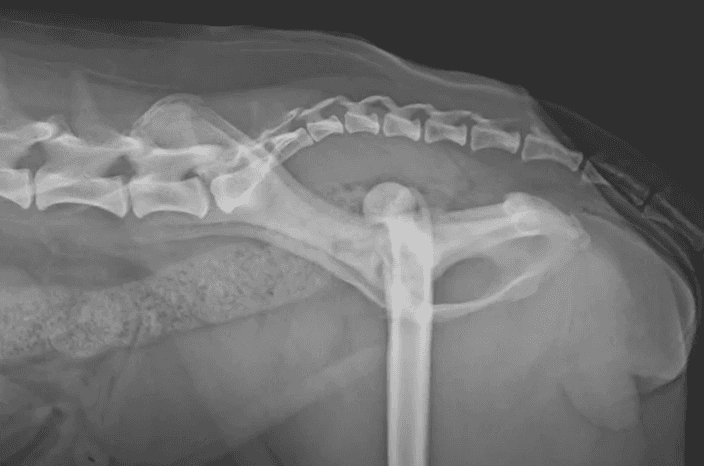

Hip Luxation

Hip luxation is the dislocation of the femoral head from the acetabulum due to trauma or a fall. Significant damage to the supporting soft tissues and sometimes the bone occurs.

The dislocation is categorized based on the direction of displacement, either craniodorsal (above the pelvis) or ventral (below the pelvis). Craniodorsal luxation is by far the most common (~90% of cases) while ventral luxation is seen more often in small breed dogs. Pets with underlying hip dysplasia are at higher risk for hip luxation because of the abnormal hip conformation.

Animals with hip luxation are typically very painful and bear little to no weight on the affected limb. The leg may appear tucked under the body or rotated abnormally when standing. Over time, mild compensation may occur, but a persistent lameness will remain because of the abnormal position of the femoral head.

Diagnosis is confirmed with radiographs of the pelvis, though the condition can often be suspected based on physical examination findings.

Substantial force is required to cause a hip luxation in a normal joint, so associated injuries to the lungs, urinary tract, or other internal organs are possible. A complete physical examination and diagnostic workup are essential to identify any concurrent injuries. Bloodwork and radiographs of the chest, abdomen, pelvis, and other affected joints are often recommended.